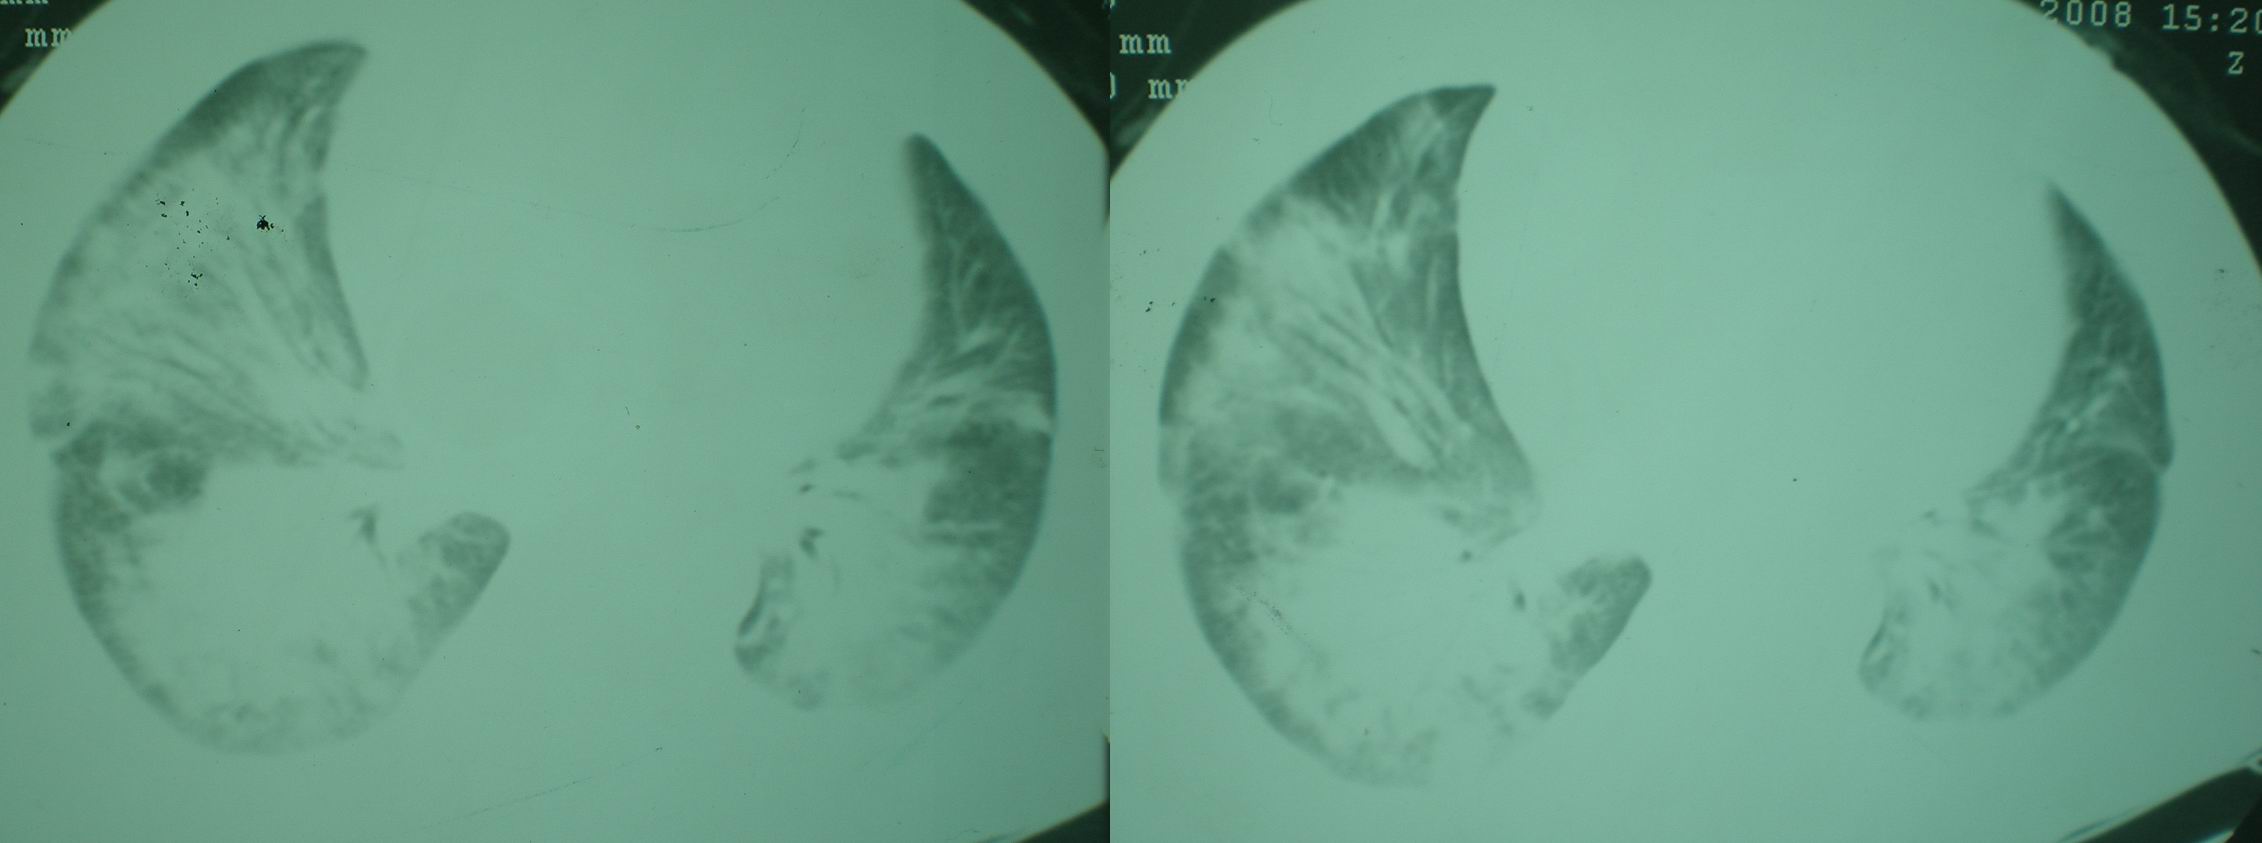

2008年11月18日今天的ct片

2008年9月18日ct片

2008年9月8日ct片:

机遇性感染!不除外急性肺水肿!

急性心衰所致肺水肿,双侧胸腔积液,少量心包积液可能?结合临床及其它检查.

我仔细看了下病人的出院小结,当时情况危急,诊断里有1型呼衰。心包周围的是脂肪密度。结合三次ct扫描的图象分析,个人认为:1、病人目前肺部病灶基本消失,双侧胸腔内少量积液,抗结核治疗才一个多月,就算是结核,抗结核治疗有效果,为何效果如此好,一点纤维灶的痕迹都没有呢,再就是患者做过气管镜检查及活检、痰检均未找到结核的证据。所以不支持结核的诊断。

2、结合现在的ct片,考虑:肺水肿及真菌感染,双侧胸腔积液。

急性呼吸窘迫综合征,肺水肿,与激素减量太快有关.双侧胸腔积液.